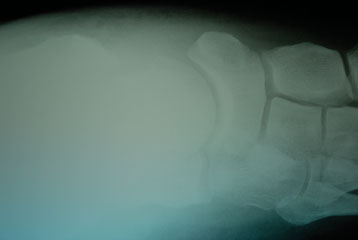

One must use intraoperative fluoroscopic imaging to demonstrate ideal alignment and the position of the fixation. Use lateral imaging of the hindfoot/ankle to assess the talocalcaneal relationship as well as the screw position and length. A dorsal to plantar view of the foot enables one to assess the talocalcaneal angle, midtarsal alignment and the talus to first metatarsal alignment. Surgeons should also obtain ankle mortise views to confirm position of the screws in the talar body and neck. Avoid a common malposition of the lateral screw into the lateral gutter of the ankle joint.